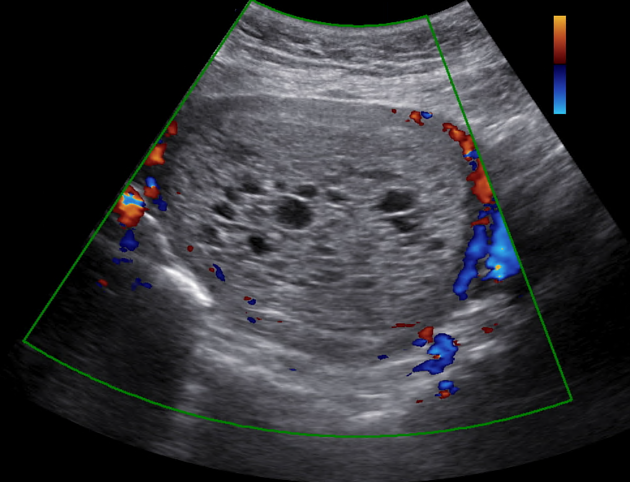

What are we seeing in this image?

Rhombencephalon